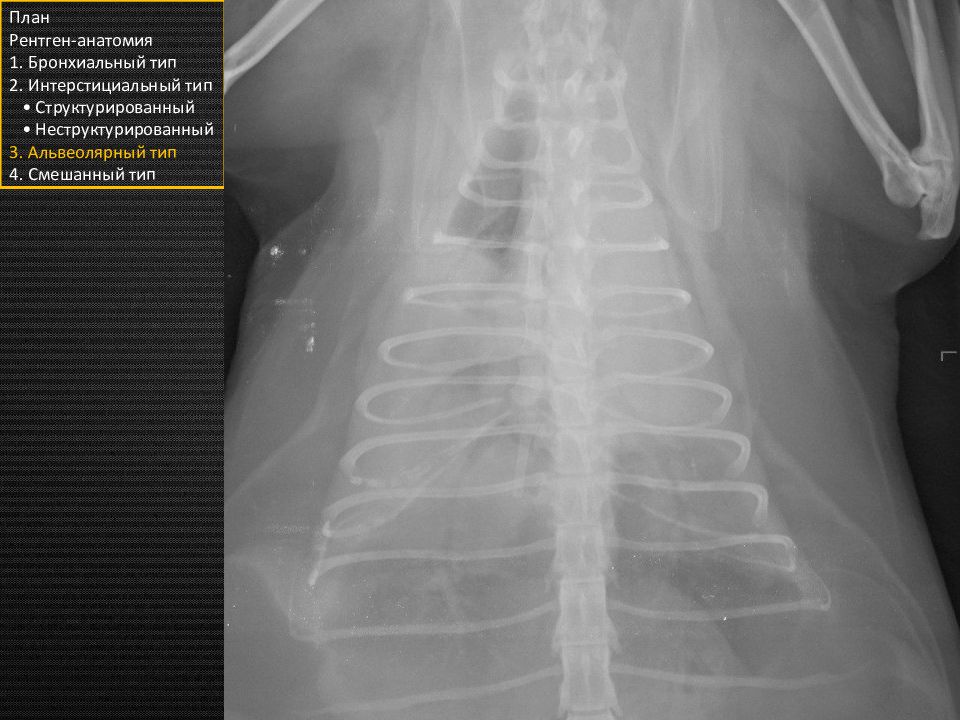

Слайд 6

Прямая проекция План Рентген-анатомия 1. Бронхиальный тип 2. Интерстициальный тип • Структурированный • Неструктурированный 3. Альвеолярный тип 4. Смешанный тип